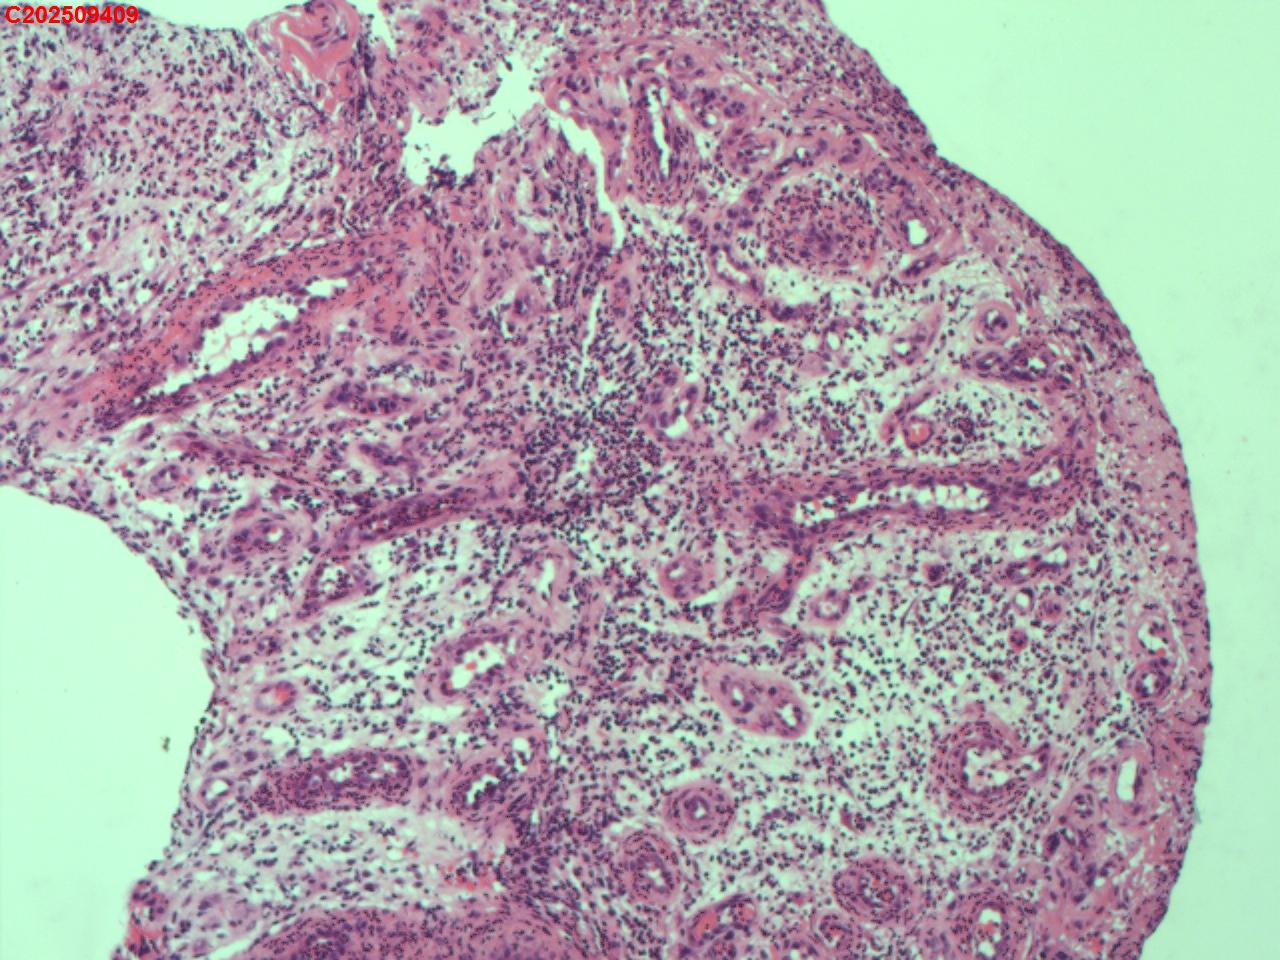

纤支镜咬检

性别年龄62岁临床诊断社区获得性肺炎,肺占位性病变带除外

一般病史胸部CT:双肺可见多发斑片状、结节状高密度影,右肺上叶及左肺下叶病灶内见多发空洞,右侧少量胸腔积液。

标本名称纤支镜咬检

大体所见纤支镜:气管通畅,隆突锐利。右肺主支气管通畅,右肺上叶见少量痰液,负压吸引后见上叶开口干酪坏死物质附着,上叶各段级支气管通畅未见新生物及坏死物质,中叶、下叶背段支气管通畅,下叶基底段见新生物阻塞气道,粘膜无充血。左肺主支气管、上叶、下叶及各段级支气管通畅,粘膜无充血,未见新生物及坏死物。

考虑:支气管炎性息肉